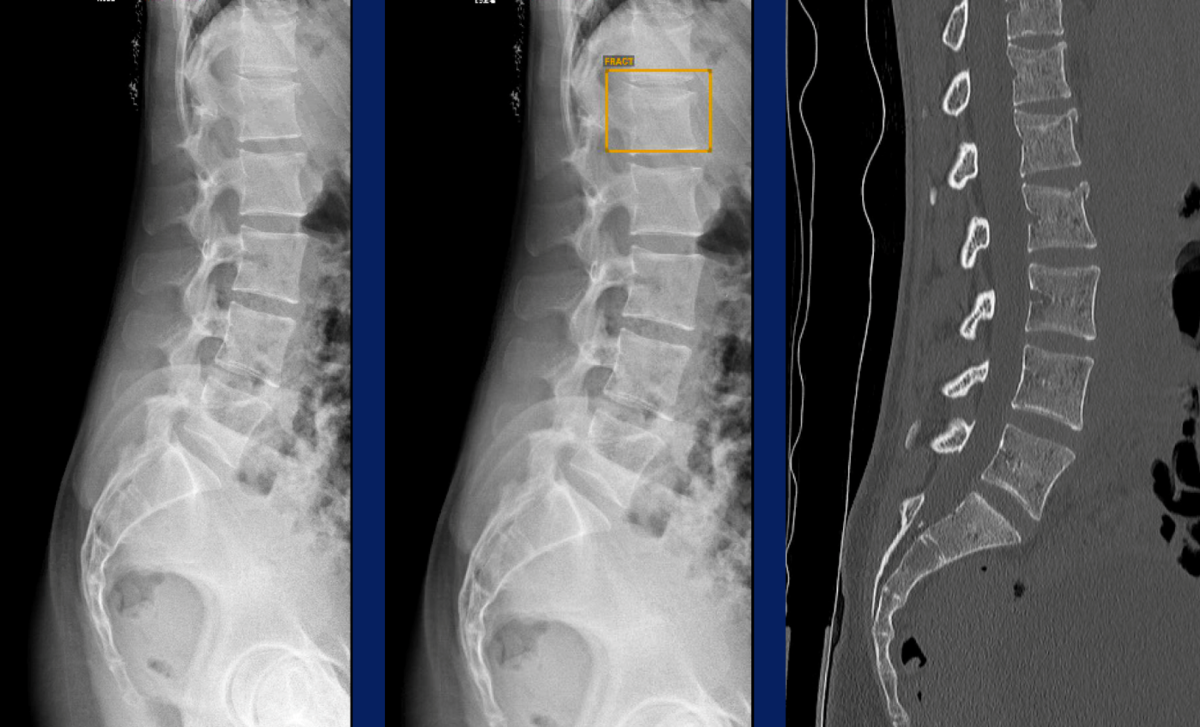

Constat : les erreurs de l’IA en pratique clinique sont fréquentes (lors de la session sont présentés des dossiers d’erreurs d’une garde de la semaine dernière, notamment le cas clinique présentée ci-dessous).

Cas clinique : fractures du corps de T12 et L2 manquée par l’intelligence artificielle, confirmée par le TDM. Seule la fracture du corps de L1 est diagnostiquée par IA. Cas présenté par le Dr TALAMARD.